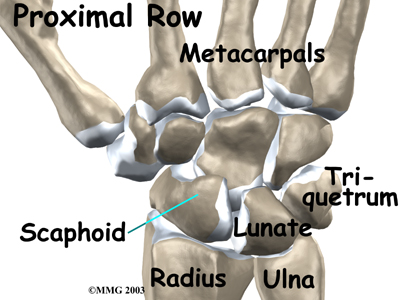

There are 15 bones that form connections from the end of the forearm to the hand. The wrist itself contains eight small bones, called:

These bones are grouped in two rows across the wrist. The

is where the wrist creases when you bend it. Beginning with the thumb-side of the wrist, the proximal row of carpal bones is made up of the scaphoid, lunate, and triquetrum. The second row of carpal bones, called the:

The proximal row of carpal bones connects the two bones of the forearm, the radius and the ulna, to the bones of the hand. The bones of the hand are called the

metacarpal bones. These are the long bones that lie within the palm of the hand. The metacarpals attach to the phalanges, which are the bones in the fingers and thumb.

One reason that the wrist is so complicated is because every small carpal bone forms a joint with the bone next to it. This means that what we call the wrist joint is actually made up of many small joints.

As its name suggests, the ulnar collateral ligament (UCL) is on the ulnar side of the wrist. It crosses the ulnar edge (the side away from the thumb) of the wrist. It starts at the ulnar styloid, the small bump on the edge of the wrist (on the side away from the thumb) where the ulna meets the wrist joint. There are two parts to the cord-shaped UCL. One part connects to the pisiform (one of the small carpal bones) and to the transverse carpal ligament, a thick band of tissue that crosses in front of the wrist. The other goes to the triquetrum (a small carpal bone near the ulnar side of the wrist). The UCL adds support to a small disc of cartilage where the ulna meets the wrist. This structure is called the triangular fibrocartilage complex (TFCC) and is discussed in more detail below. The UCL stabilizes the TFCC and keeps the wrist from bending too far to the side (toward the thumb).

The radial collateral ligament (RCL) is on the thumb side of the wrist. It starts on the outer edge of the radius on a small bump called the radial styloid. It connects to the side of the scaphoid, the carpal bone below the thumb. The RCL prevents the wrist from bending too far to the side (away from the thumb).

At the wrist, the end of the ulna bone of the forearm articulates with two carpal bones, the lunate and the triquetrum.